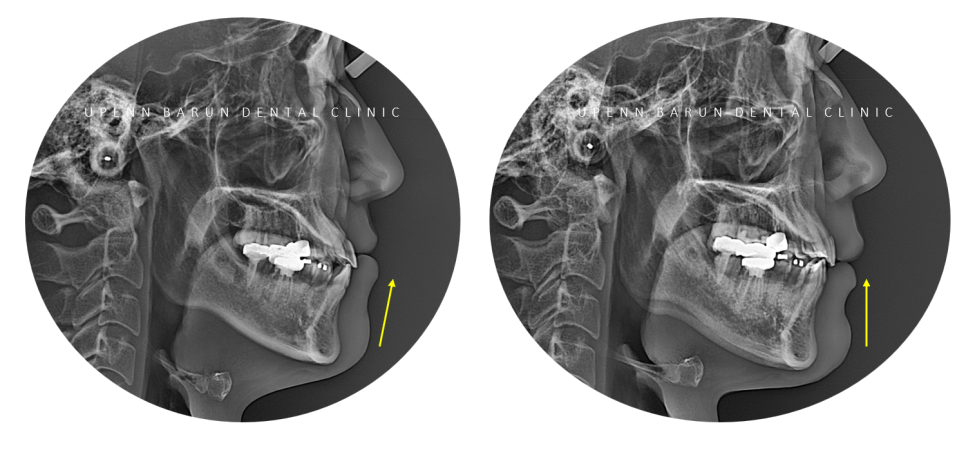

반대교합으로 아래턱이 도드라져 보였던 이전과는 달리

잠실교정치과

비발치인비절라인으로

반대교합이 개선되면서

옆모습의 입술과 턱라인이 정리된 모습입니다 :)